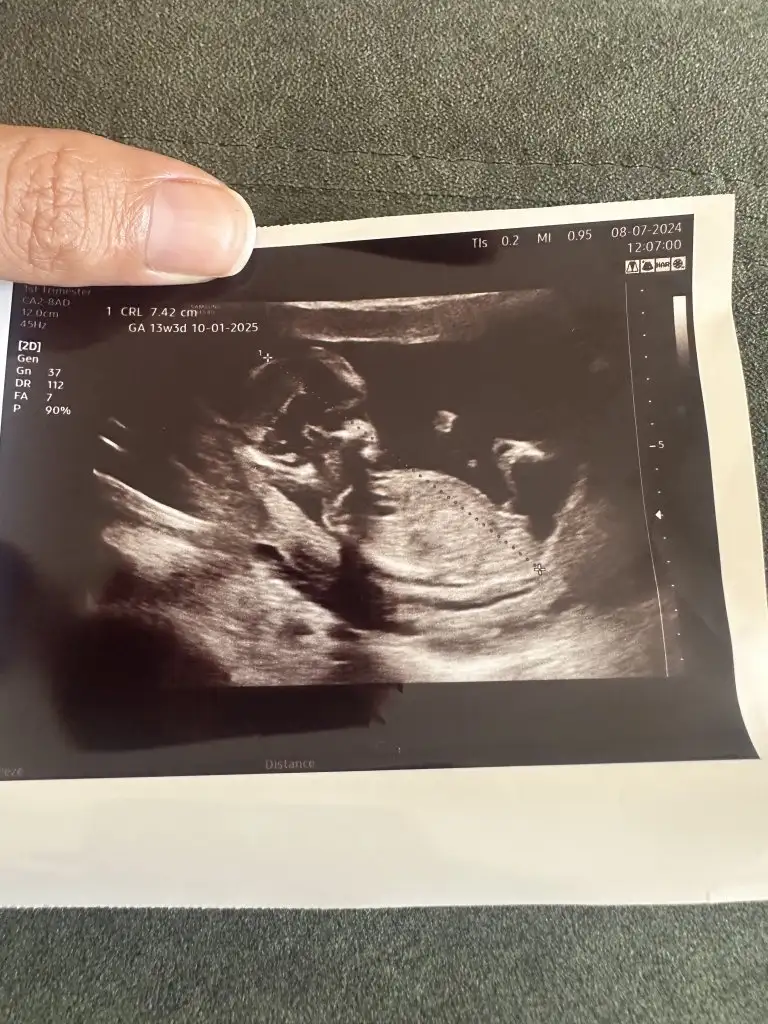

Hangi siteden baktırmıştınız acaba ?Ben Instagram dan baktırmıştım, tahminim %70 kız demişti, dün Dr %99 erkek dedi

Bugün gittim canım kız dedi doktorSanki çıkıntısı var erkek gibi duruyor

Ama çok erkek gibi duruyo yaBuda bugünün ultrasonu doktor kız dedi ama gören erkek diyor sizce ne